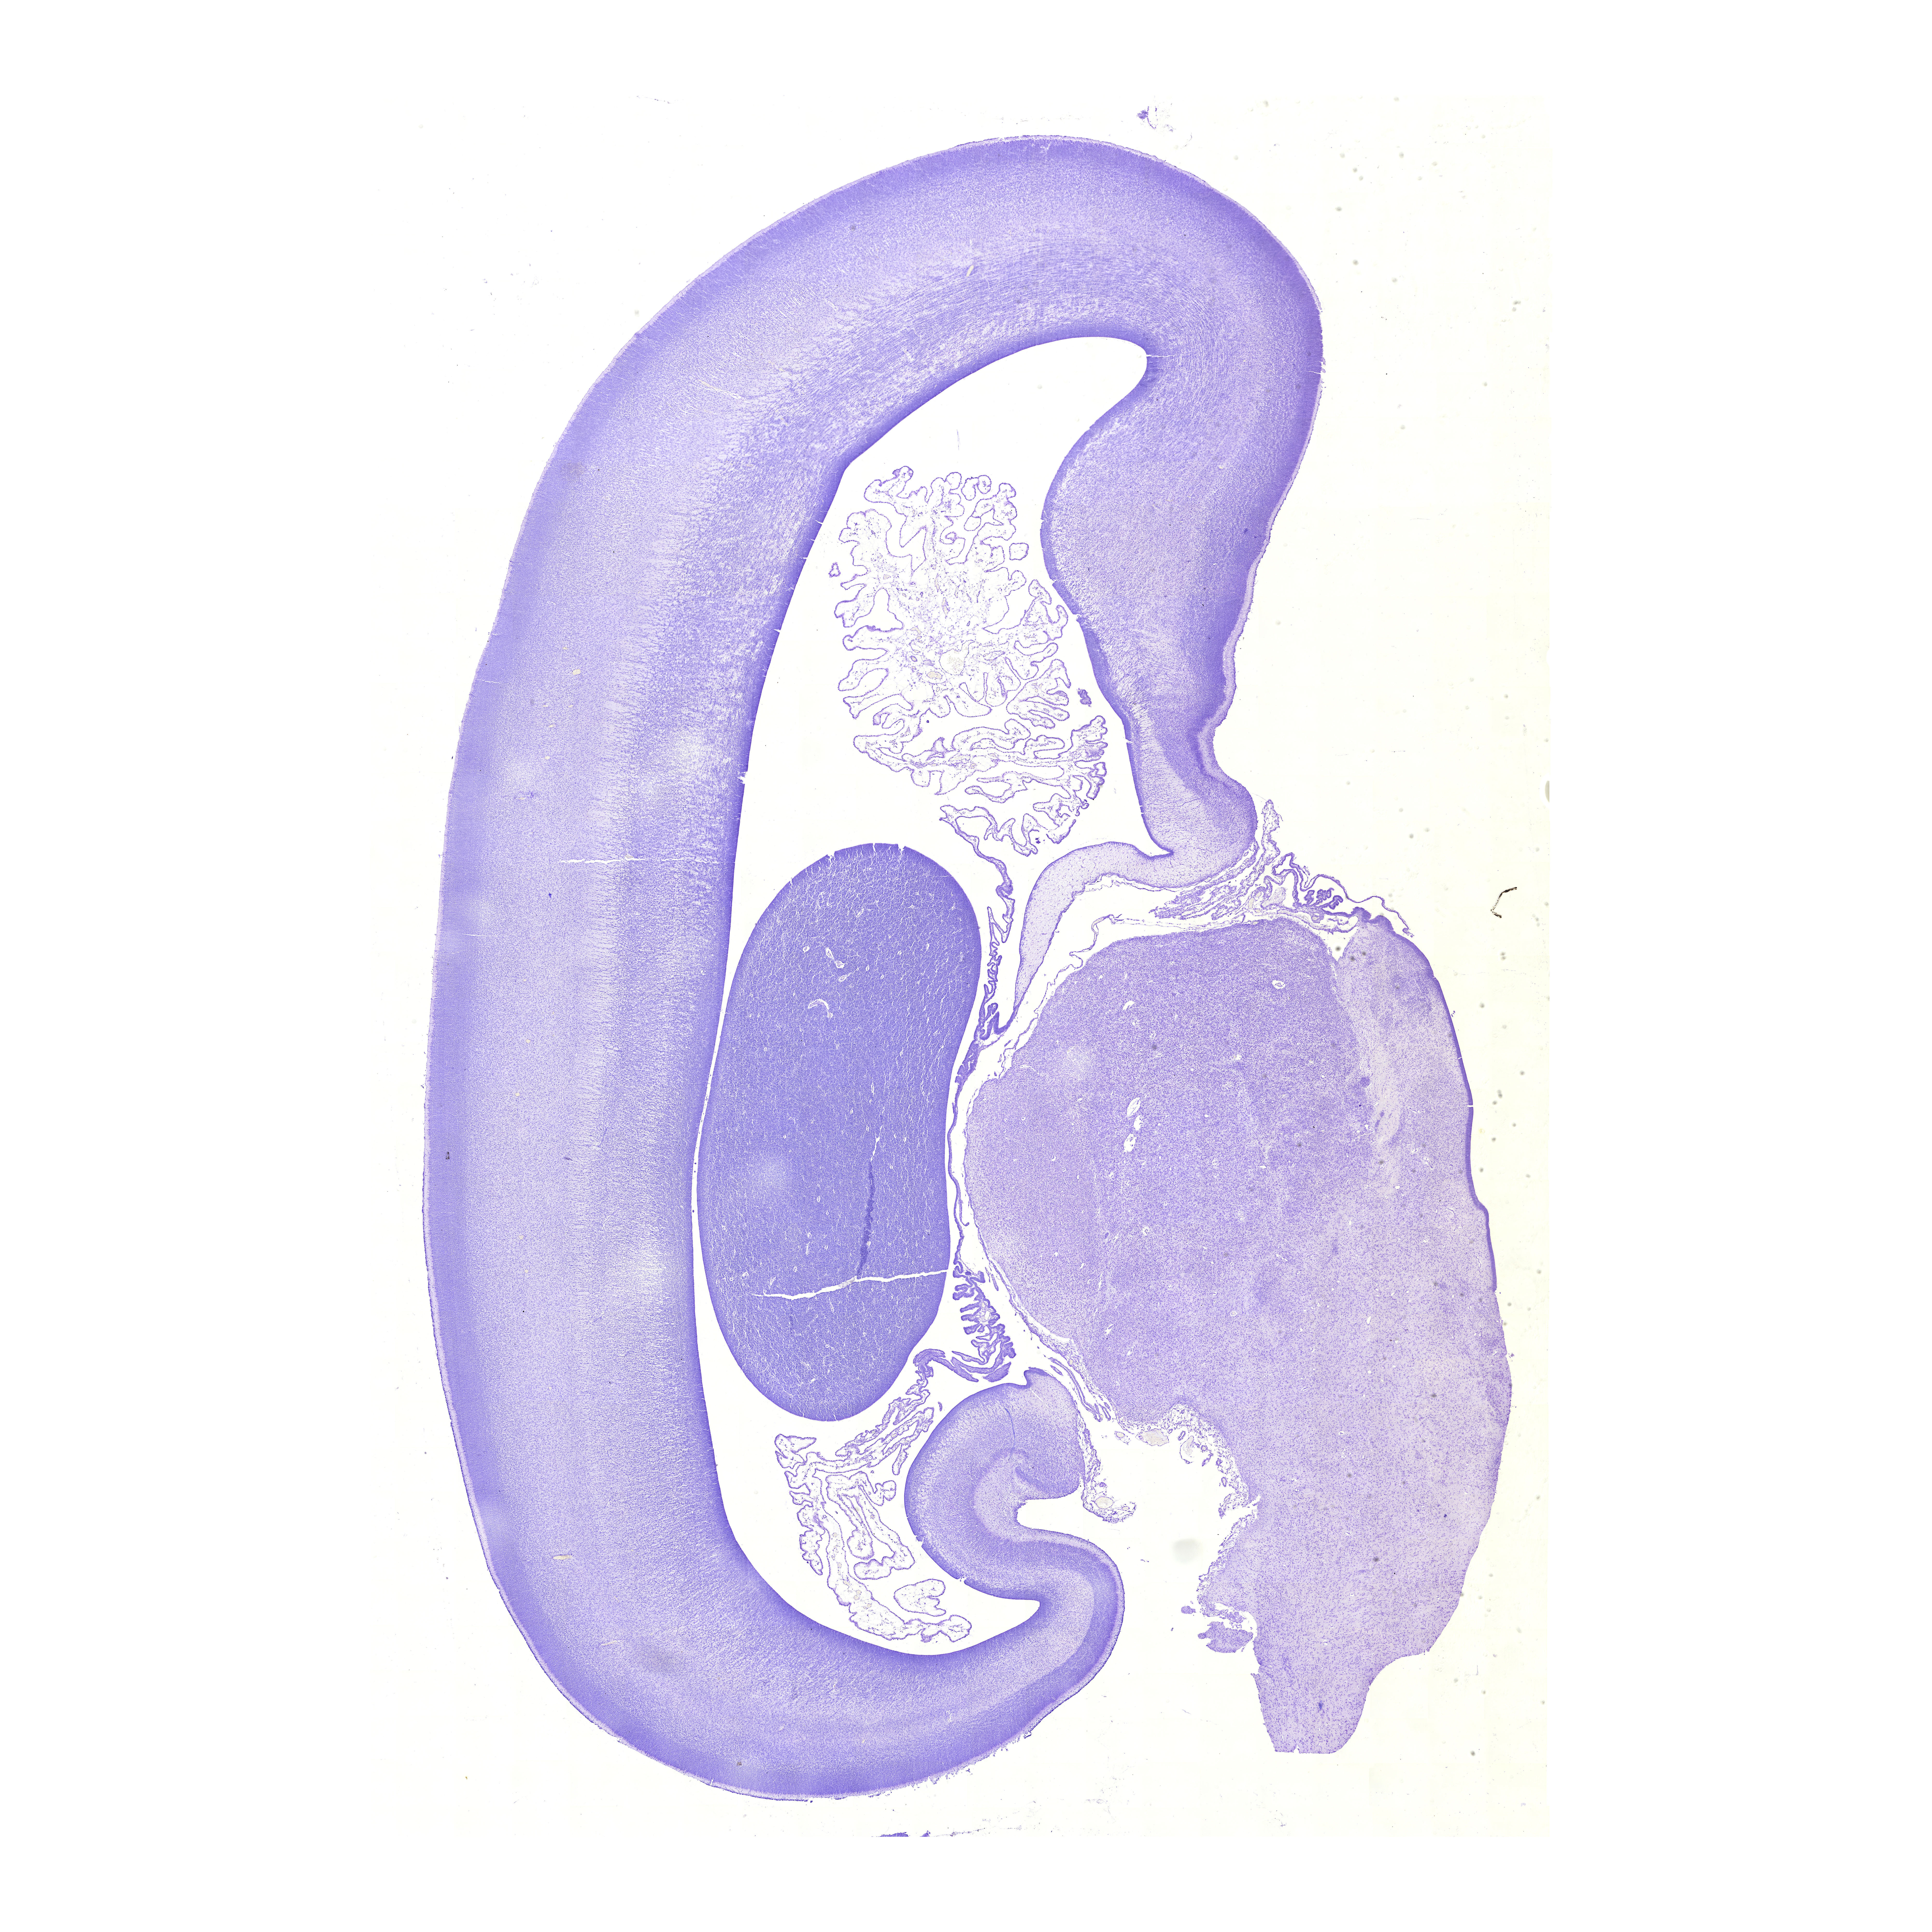

16th gw

Nissl (№1)